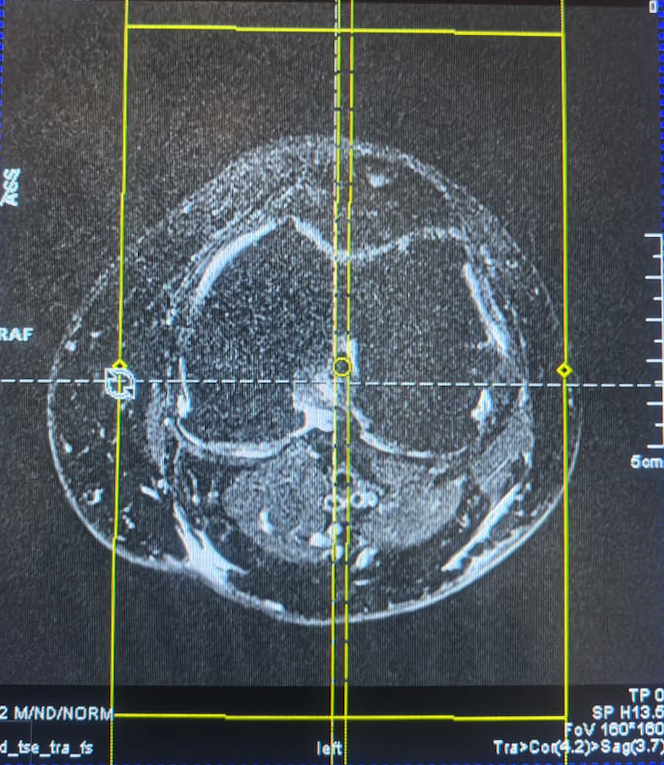

Артефакты на коленной катушке 14CH Extremity Coil — 10353300

14CH Extremity Coil — 10353300

Типовые проблемы Siemens

1. Выход из строя предусилителей (preamps)

Это наиболее частая причина артефактов и «уходящей» частоты. Предусилители теряют параметры, начинают вносить усиление с искажениями, или вовсе не усиливают — и система интерпретирует это как шумовой канал.

3. Проблемы в антенной части

Каждый элемент антенны — часть общего контура. Любое отклонение вызывает локальные артефакты.